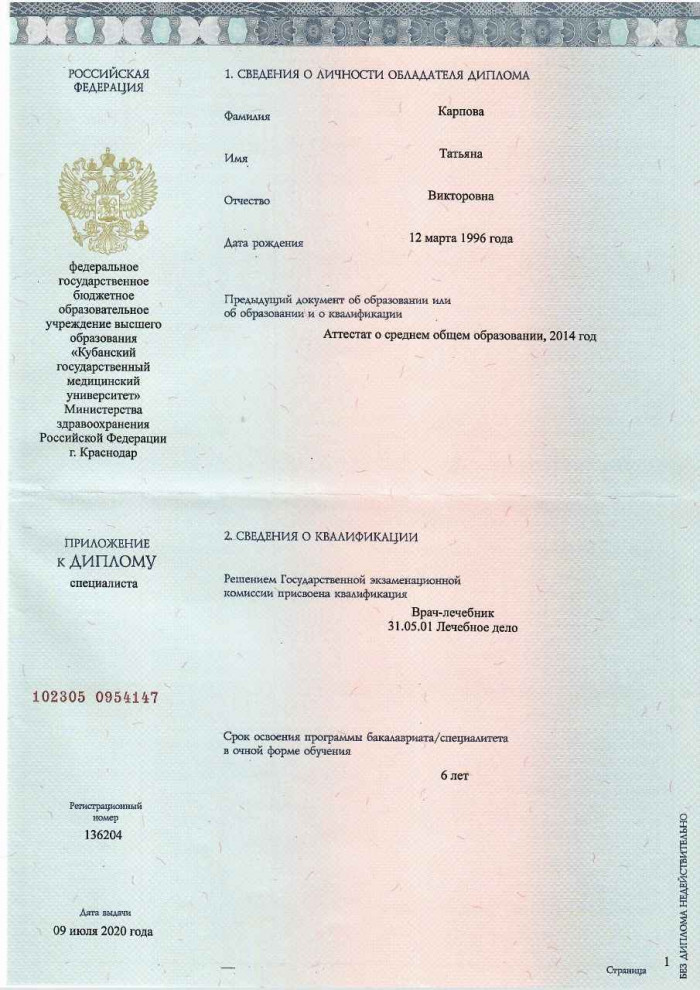

Лицензии и сертификаты нашей клиники

Медицинские услуги оказываются ООО "ЮгЭкоСервис+" по лицензии ЛО-61-01-008143 от 28.12.2021 г.